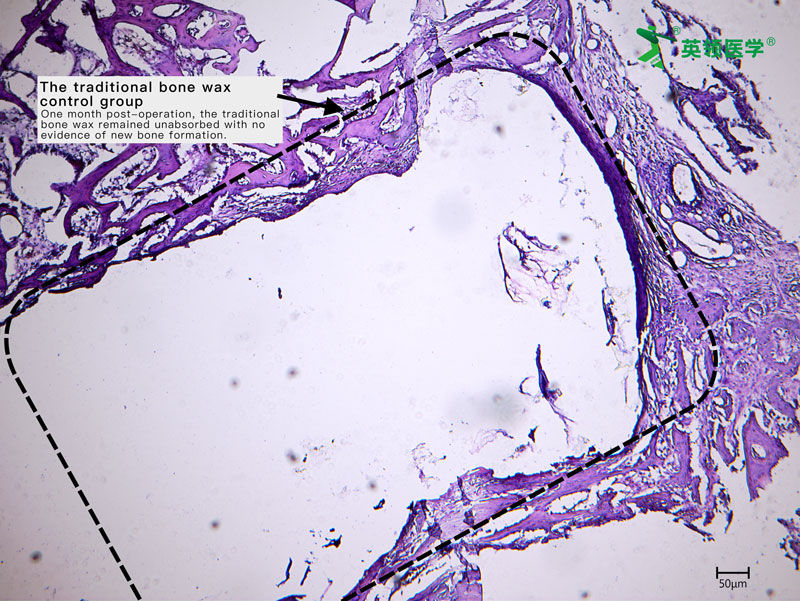

During the trial, ABHM demonstrated excellent clinical performance and safety. Its biodegradable properties and ease of use were highly praised by surgical experts from multiple clinical centers. The product rapidly achieves hemostasis by mechanically sealing bone wound surfaces, and it degrades completely within four weeks. This effectively avoids complications associated with traditional bone wax, such as impaired bone healing, foreign body granuloma, chronic inflammation, and infection—offering a safer and more physiologically compatible solution for bone wound management.